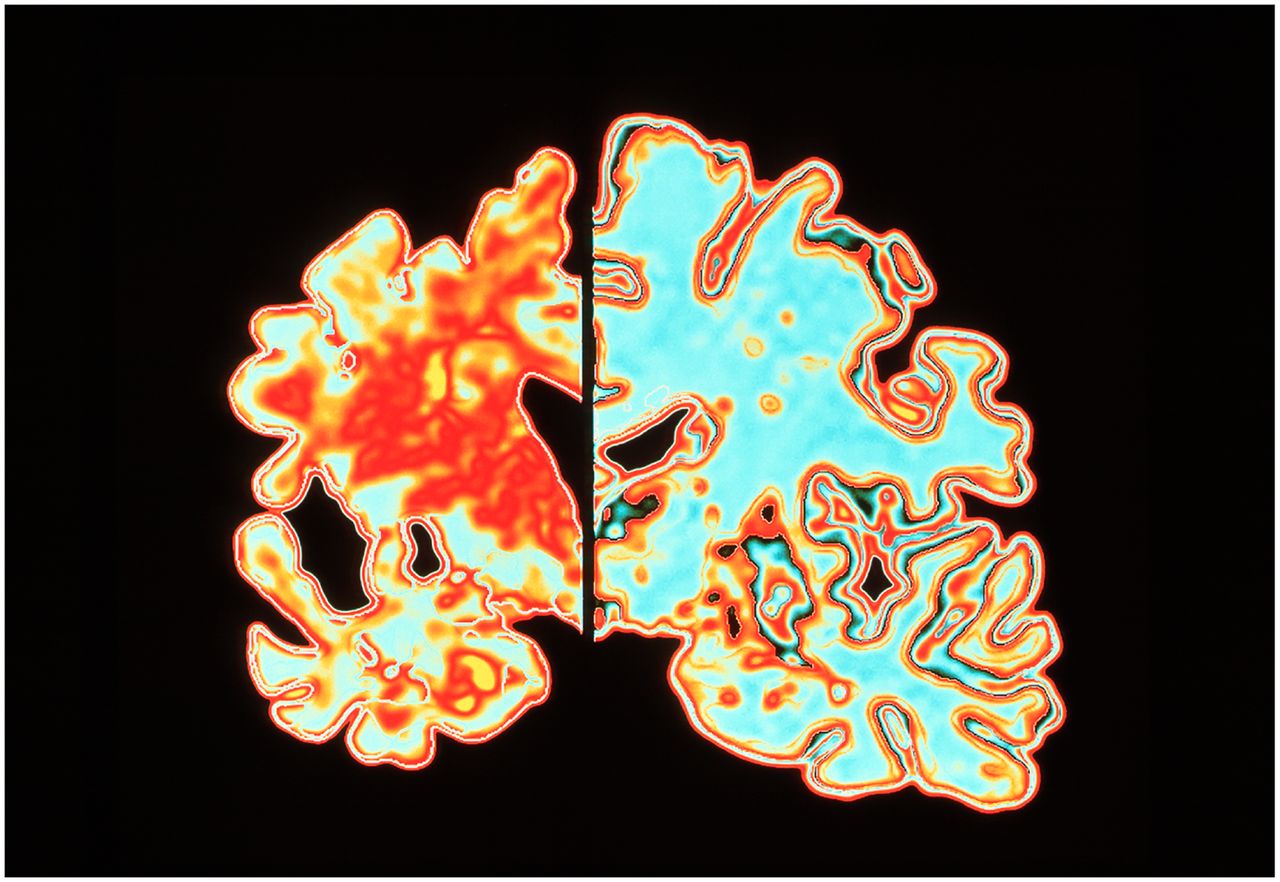

A coronal slice from a patient with Alzheimer’s disease (left), compared with a normal brain (fight). Image: Science Source/Alfred PasiekaThe FDA is expected to decide by June 7 whether or not to approve Aducanumab, a human monoclonal antibody that targets the underlying cause of Alzheimer’s disease. Aducanumab is a monthly intravenous infusion therapy. The drug targets beta-amyloid, or chains of amino acids that are the main component of the amyloid plaques found in the brains of people with Alzheimer's disease.Based on clinical data, Aducanumab addresses the underlying cause of Alzheimer’s, potentially slowing cognitive and functional decline. https://investors.biogen.com/news-releases/news-release-details/biogen-and-eisai-announce-fdas-3-month-extension-review-period If approved, Aducanumab would be the first treatment to meaningfully change the course of this debilitating and ultimately fatal disease.Aducanumab was first created by Dr. Roger Nitsch and Dr. Christoph Hock at Neurimmune, a biopharmaceutical company headquartered in Zurich. Nitsch and Hock developed Aducanumab with a team of researchers at the University of Zurich and licensed it to the biotech company, Biogen. Scientists at Neurimmune began their drug discovery process by studying “super-agers”—people in their 70s and 80s who have the mental or physical capability of their decades-younger counterparts. The team then used these patients' memory B-cells to purify auto-antibodies which can detect and destroy amyloid beta oligomers, small assemblies of amyloid beta protein associated with Alzheimer's disease.